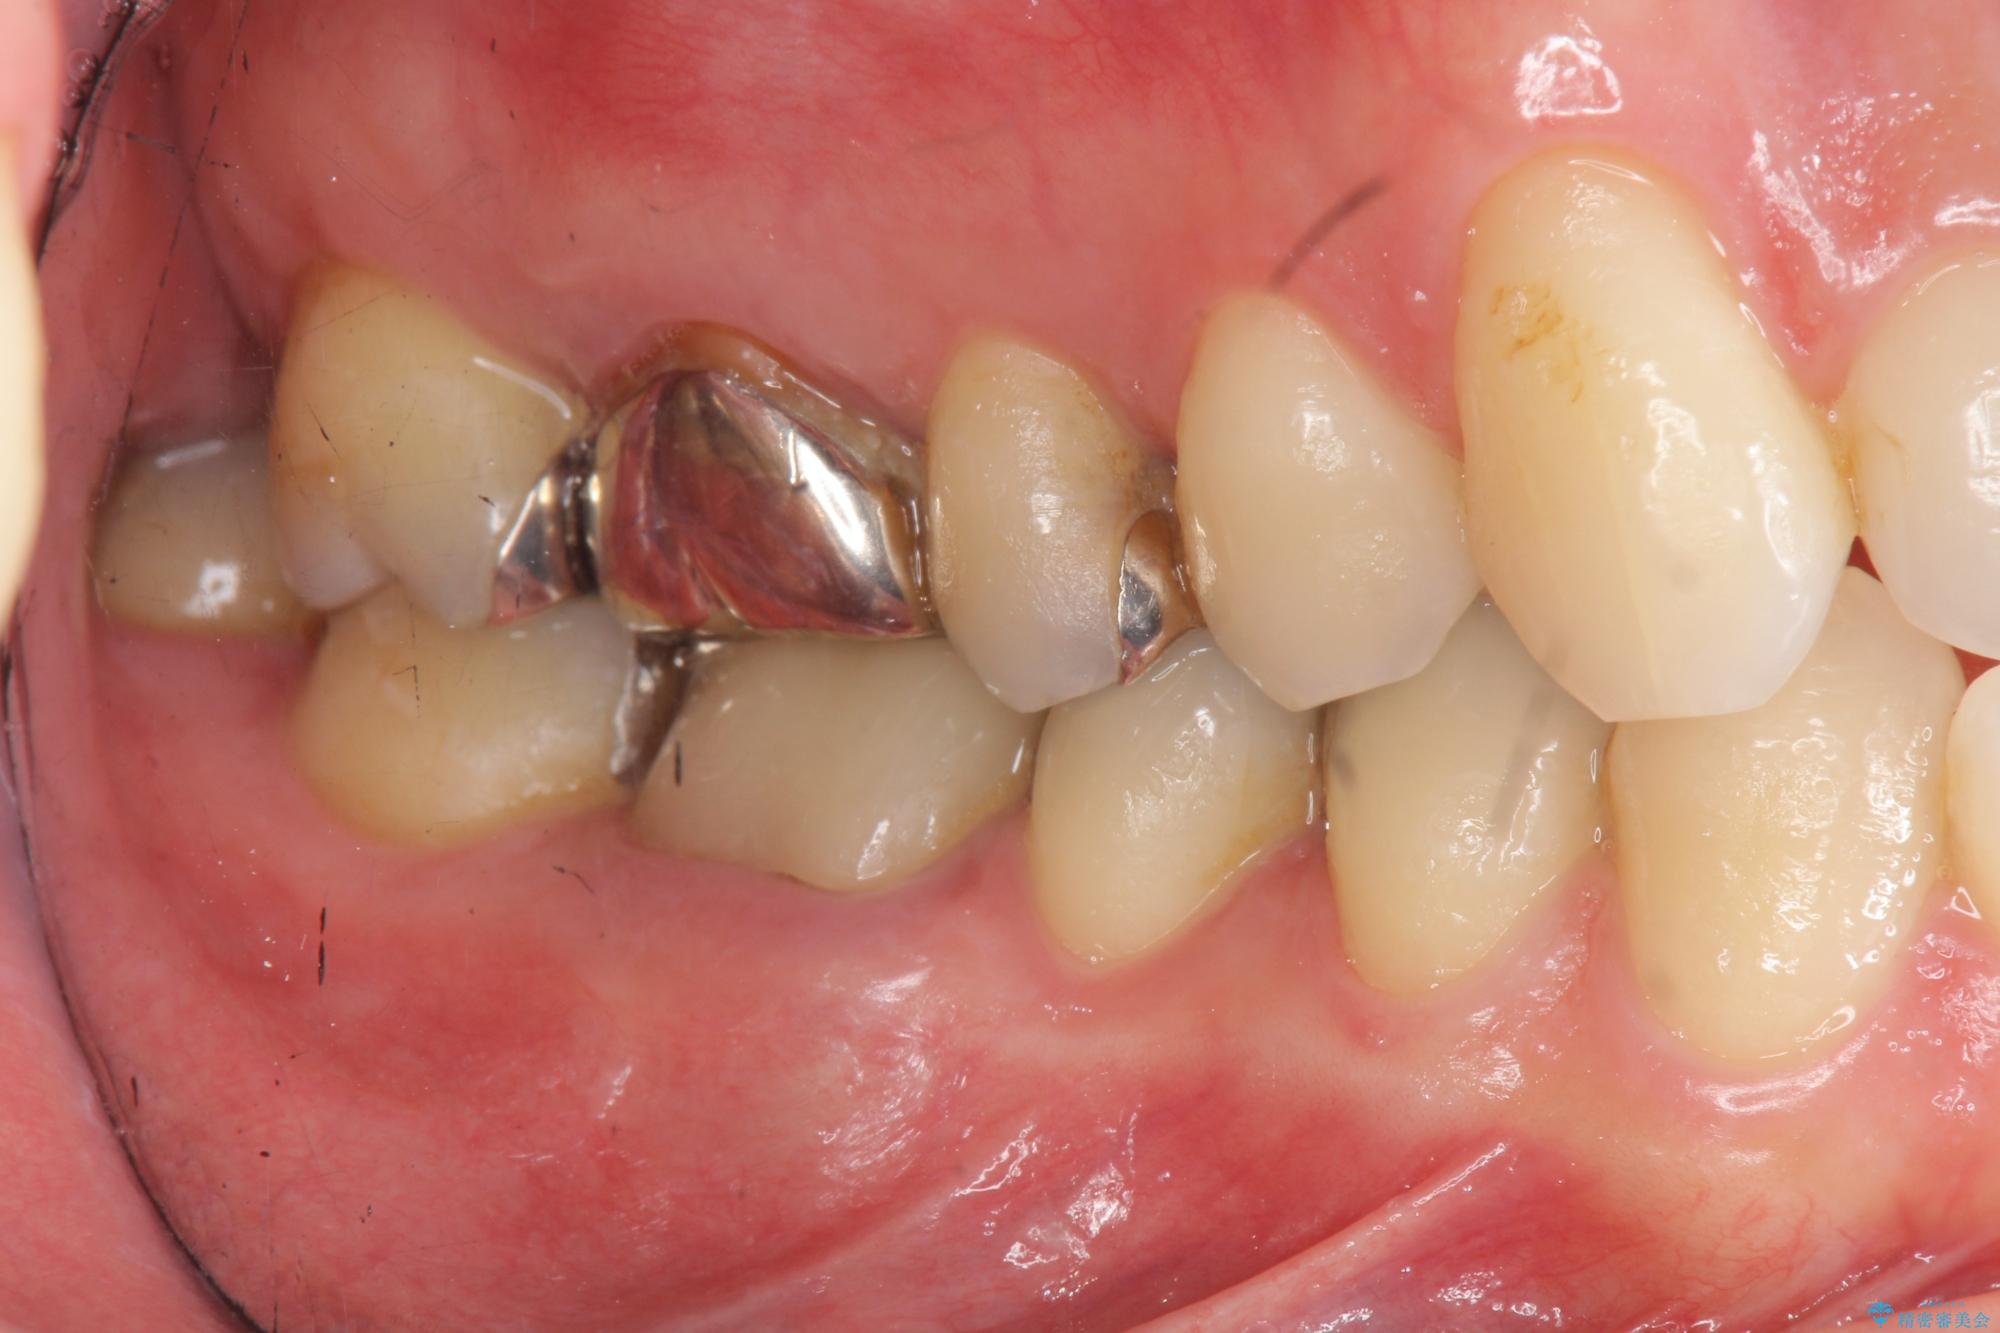

- 突き出た前歯の角度の改善と虫歯治療の改善を求めて来院されました。

虫歯を除去したのち、マウスピース矯正治療を行い、歯並びやがたつきを改善したのち、セラミックに置き換えることで審美性の向上を計画します。